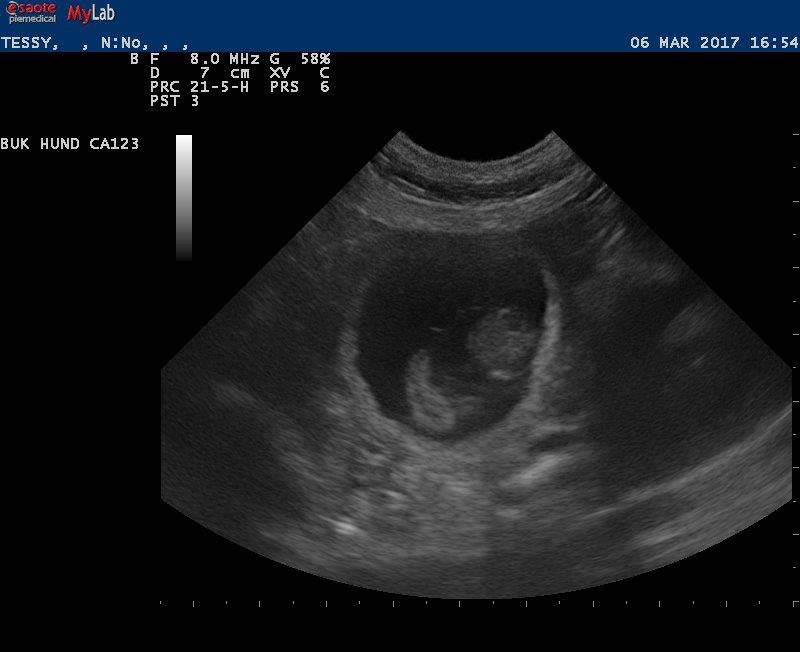

Vi hoppas så mycket på att Lotta och Bertil ger oss ett gäng valpar i mitten på januari!

Här kommer en bild på Lotta och Bertil. Vi kan göra ultraljud om en dryg vecka, håll tummarna!